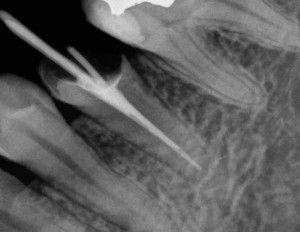

③ 歯の根っこの中の消毒が完全に終わり、症状もなければ、防腐剤(充填材)を隙間のないようきれいにつめます。

④ 土台(コア)をいれて、虫歯を取って空洞になっている歯を補強します。

⑤ かぶせものを入れて治療が完了します

治療後:セラミックスクラウン(保険外)